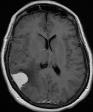

Machine learning has been widely adopted for medical image analysis in recent years given its promising performance in image segmentation and classification tasks. The success of machine learning, in particular supervised learning, depends on the availability of manually annotated datasets. For medical imaging applications, such annotated datasets are not easy to acquire, it takes a substantial amount of time and resource to curate an annotated medical image set. In this paper, we propose an efficient annotation framework for brain MR images that can suggest informative sample images for human experts to annotate. We evaluate the framework on two different brain image analysis tasks, namely brain tumour segmentation and whole brain segmentation. Experiments show that for brain tumour segmentation task on the BraTS 2019 dataset, training a segmentation model with only 7% suggestively annotated image samples can achieve a performance comparable to that of training on the full dataset. For whole brain segmentation on the MALC dataset, training with 42% suggestively annotated image samples can achieve a comparable performance to training on the full dataset. The proposed framework demonstrates a promising way to save manual annotation cost and improve data efficiency in medical imaging applications.

翻译:近年来,由于在图像分割和分类任务方面表现良好,医学图像分析广泛采用了机器学习。机器学习的成功,特别是监督学习的成功,取决于手动附加说明数据集的可用性。对于医疗成像应用来说,这种附加说明数据集不容易获得,需要大量的时间和资源来翻译附加说明的医学成像集。在本文件中,我们建议为大脑MR图像建立一个高效的注释框架,为人类专家提供信息性样图像,供人类专家作说明。我们评估了两种不同的大脑图像分析任务的框架,即脑肿瘤分割和整个大脑分割。实验显示,对于BRATS 2019数据集的脑肿瘤分割任务,培训一个只有7%的附加说明图像样本的分解模型,其性能与全数据集培训的性能相当。对于MALC数据集的整个大脑分割,用42%的附加说明性图像样本进行的培训,可以实现与全数据集培训的类似性能。拟议的框架展示了节省人工注解成本和提高医疗成像应用数据效率的有希望的方法。